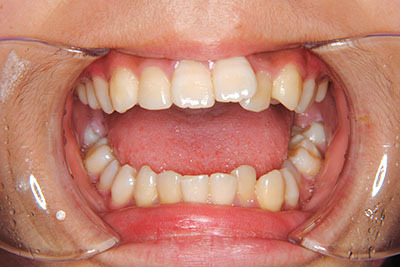

小学生高学年や中高生で矯正治療を考えている方へ

歯が乳歯から永久歯に生え変わった小学生高学年や、中高生でも矯正治療に手遅れということは全くありません。

成長中の顎の骨を矯正できたり、この時期の矯正はおとなになってから矯正治療を始めるよりも短期間で済むことがほとんどです。当院だとおおよそ1年で動的治療(マルチブラケット装置をつける期間)が終わることが多いです。